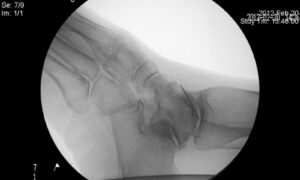

关节痛

微信讲课:膝关节骨关节炎与富血